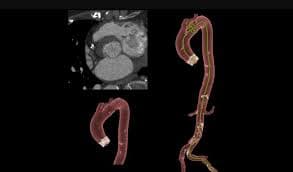

Coronary Angiogram

A CT Coronary Angiogram is a non-invasive imaging test that uses a CT scanner, and contrast dye to create detailed 3D pictures of your heart's arteries, revealing plaque, blockages, or narrowing (stenosis) that can cause heart problems like chest pain.

3D Vessel Analysis